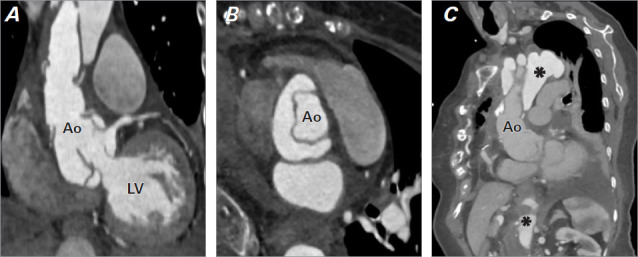

这个新颖的病例记录了一名 75 岁女性患者在修复升主动脉瘤后,成功使用经导管主动脉瓣植入术治疗主动脉根部夹层引起的严重主动脉瓣关闭不全。在她出现充血性心力衰竭症状后,检查发现了新的严重主动脉瓣关闭不全和急性主动脉夹层。考虑到再次手术的风险过高,患者接受了 27 毫米的 Portico(St Jude Medical)自扩张人工主动脉瓣手术,结果临床症状大为改善,且未出现手术并发症。该病例凸显了经导管主动脉瓣植入术在治疗复杂主动脉疾病方面的多功能性,并强调了多学科评估和谨慎选择人工瓣膜的关键作用。

This novel case documents the successful use of transcatheter aortic valve implantation to treat severe aortic insufficiency arising from aortic root dissection following the repair of an ascending aortic aneurysm in a 75-year-old female patient. After she presented with symptoms of congestive heart failure, investigation revealed new severe aortic insufficiency and an acute aortic dissection. Given the prohibitive risks of reoperation, a self-expanding 27-mm Portico (St Jude Medical) prosthetic aortic valve was deployed, resulting in substantial clinical improvement without procedural complications. This case highlights the versatility of transcatheter aortic valve implantation in managing complex aortic disease and emphasizes the critical role of multidisciplinary evaluation and careful prosthesis selection.